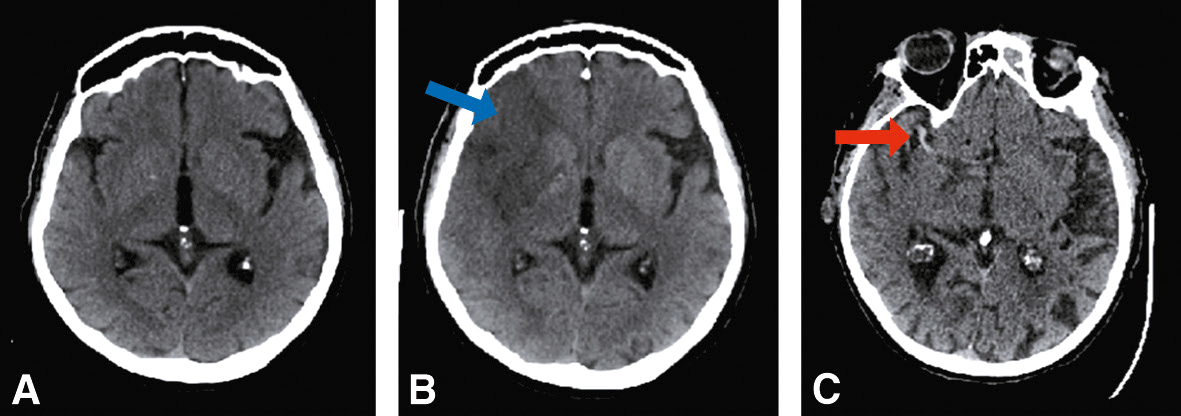

Fig. 28.13 Figure Signes précoces d’ischémie cérébrale en scanner sans injection.

A. Scanner cérébral normal. B. Hypodensité systématisée au territoire sylvien, effacement partiel du noyau lenticulaire et effacement des sillons corticaux hémisphériques droit (flèche bleue). C. Hyperdensité spontanée de l’artère cérébrale moyenne droite (signe de la sylvienne blanche ou « trop belle artère » – flèche rouge).

2 Scanner sans injection

a Dans les premières heures

Il présente les caractéristiques suivantes :

• • en cas d’infarctus cérébral :

• – souvent normal,

• Figure signes précoces possibles (fig. 28.13) :

• – effacement des sillons corticaux,

• – dédifférenciation substance blanche/substance grise : atténuation du manteau cortical de l’insula, atténuation du noyau lenticulaire,

• – hyperdensité artérielle (artère sylvienne « trop belle ») témoignant du thrombus dans l’artère;

• Figure en cas d’hémorragie intraparenchymateuse : hyperdensité spontanée dont on précisera la localisation lobaire ou profonde.

b Au-delà de la 6e heure

• • L’hypodensité de l’infarctus cérébral apparaît et s’accentue les premiers jours :

• Figure elle est systématisée au territoire artériel infarci (fig. 28.13);